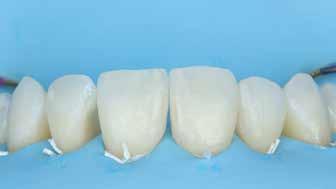

A cikkünkben bemutatásra kerülő eset ellátása során preparációt héjak készre vitele során a platinafólia technikát alkalmaztuk.

kívül vékonyak, és ezáltal a végleges rögzítésük előtt jelentős olyan minimál invazív kezelési eljárásnak számítanak, amely

elérni. A fent leírtak alapján bátran

preparációt nem igénylő héjak készítése mellett döntöttünk. A alkalmaztuk. Annak ellenére, hogy az elkészítésre kerülő héjak rendjelentős törésveszéllyel állunk szemben, összességében mégis amely segítségével kifogástalan esztétikai eredményeket lehet javasoljuk e módszer alkalmazását.

A fogászati kezelések során manapság már nem kizárólag az esztétikai megjelenés helyreállítására törekszünk. Sokszor a kedvezőtlen esztétikai megjelenés hátterében álló okok következményes módon a fogazat funkcionális működését is károsítják, így a kezelések során ezeknek a helyreállításával is foglalkoznunk kell. A különböző funkcionális és esztétikai diszkrepanciák kezelésére számtalan módszer létezik, ám ezen fogászati beavatkozások mindegyikében közös, hogy a kivitelezésük során nagyon szoros együttműködésre van szükség a kezelést végző fogorvos és a munkáját segítő fogtechnikus között. Az alábbi esetbemutatás során egy fiatal hölgypáciens fogazatának héjak alkalmazásával történő esztétikai és funkcionális rehabilitációját szeretnénk ismertetni.

1. és 2. ábra: A kiindulási és a befejezést követően látható állapot összehasonlítása extraorális felvételek segítségével.